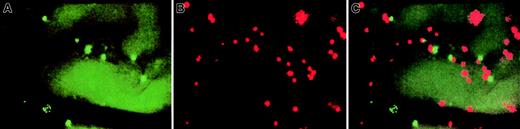

To explore the unexpected finding that selectins do not contribute to HPC rolling in irradiated BM, we analyzed endothelial surface adhesion molecule expression in live BM by using 2 sets of fluorescent beads, visualized by epifluorescence through rhodamine (NR beads) and FITC (YG beads) filters (Figure 4). One set of beads was coated with mAbs to VCAM-1, E-selectin, or P-selectin, whereas the other was conjugated to control mAb to evaluate background binding. Equivalent numbers of both sets were injected into recipient mice, and bead accumulation in skull BM vessels was recorded by IVM.

Representative intravital micrographs showing specific accumulation of anti–VCAM-1 beads and control beads in nonirradiated BM.

Equivalent numbers of control and specific mAb-coated beads were injected into the carotid artery, and beads bound to the luminal surface of the vessel wall were counted 10 to 15 minutes later using appropriate filters. (A) Accumulation of control beads (YG) in nonirradiated BM microvessels. (B) Binding of anti–VCAM-1–coated beads (NR) in nonirradiated BM microvessels (same field of view), providing evidence for constitutive expression of VCAM-1 on BM ECs. Because this field was recorded through a filter set optimized for red (rhodamine) fluorescence, the autofluorescence of extravascular tissue was much lower than in panel A, which was recorded through an FITC filter set. Thus, the outline of BM microvessels is undetectable in panel B. (C) Computer-generated overlay of panels A and B. The ratio of specific/nonspecific bead binding in this experiment was 3.7. The variability in apparent size of different beads was due, in part, to the blurring of individual beads located out of the focal plane and, in part, because some signal bleeding occurred when using SIT cameras to record intensely fluorescent particles. All scenes were recorded through a × 20 water immersion objective (Zeiss).